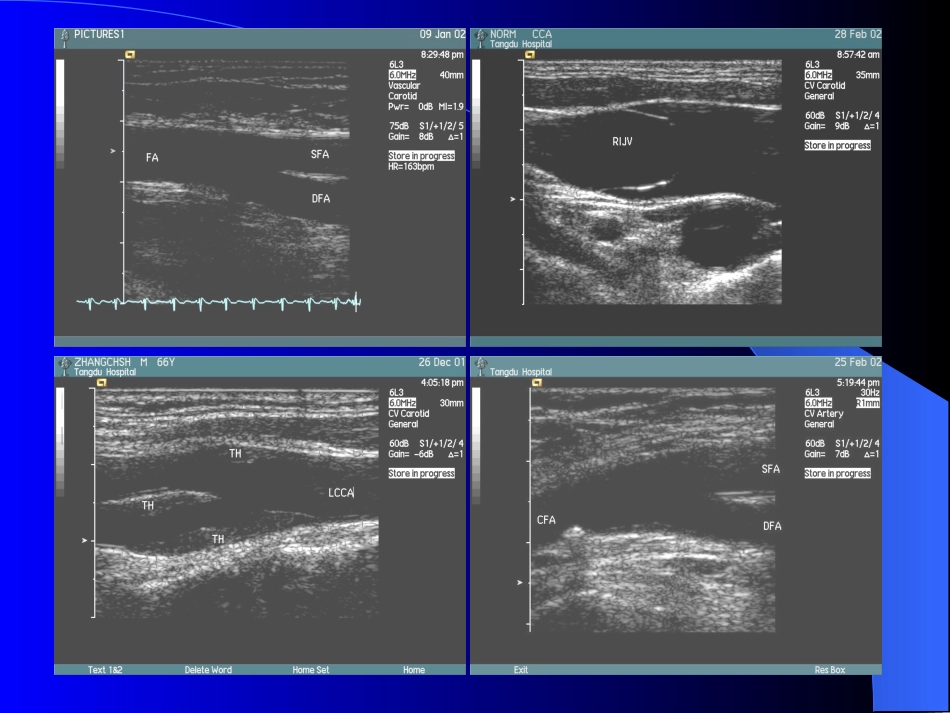

血管超声检查技术血管超声检查技术血管超声检查的观察内容:–血管走行是否正常–血管壁是否光滑、有无斑块回声、有无断裂或缺损、有无夹层–管腔内有无血栓及其他回声–彩色血流充盈是否完整–血流方向及速度有无异常颈部血管超声检查技术颈部血管超声检查技术解剖关系–颈总动脉:胸锁关节,甲状软骨上缘–颈内、颈外动脉:颈外动脉先位于前内侧,后转入前外侧;颈内动脉先位于后外侧,后转入后内侧–椎动脉:颈总动脉后外方,颈椎横突间隙内–颈内静脉:颈总动脉前外方适应症适应症颈动脉硬化(斑块形成、闭塞),颈动脉瘤(真性、假性、夹层)颈动脉体瘤椎动脉硬化(斑块形成、闭塞)原发性颈静脉扩张症,颈内静脉血栓锁骨下动脉窃血综合症颈动静脉瘘检查技术检查技术检查仪器–采用彩色多普勒超声诊断仪–选用5-10MHz的高频线阵探头–检查动脉时,彩色速度标尺约12-40cm/s,脉冲多普勒速度标尺约0-80cm/s;检查静脉时,彩色速度标尺约6cm/s,脉冲多普勒速度标尺约0-30cm/s;体位:仰卧位,颈后垫枕,头后仰;检查时,头转向对侧扫查技术扫查技术沿血管走行做横断及纵断扫查进行多普勒检测–彩色多普勒显示–脉冲多普勒显示数据测量–血管内径,血管壁厚度(中-内膜复合体厚度)–Vmax,Vmin,Vmean–RI,PI,S/D–动脉狭窄程度估计:内径减少法面积减少法束臂试验–对于疑有锁骨下动脉窃血综合症的患者应用–若出现椎动脉逆流则为阳性腹部血管血管超声检查技术腹部血管血管超声检查技术解剖关系–AA、IVC:剑突与脐之间,脊柱的两旁–CA及分支:胰腺上缘水平,“Y”型(海欧征)–SMA:CA下方1cm处–KA:CA下方1-1.5cm处–髂动静脉及分支:脐下水平,与腹正中线成角约25-35度–PV系统:MPV:IVC前方,在胰颈后方由SPV、SMV汇合SPV:胰腺后方SMV:胰钩突前方–HV:第二肝门处汇入ICV,左、中、右三支–KV:LKV经SMA与AA之间汇入ICV适应症适应症动脉疾病:动脉瘤(真性、假性、夹层)、动脉硬化(斑块形成、闭塞)、肾动脉狭窄、结节性多动脉炎、急性动脉栓塞等静脉疾病:静脉栓塞、IVC肝段阻塞综合症、IVC综合症、髂总静脉受压综合症等其他:动静脉瘘、腹腔内管状结构的鉴别、移植脏器(肝、肾)的血流监测等检查技术检查技术检查前准备:空腹,必要时灌肠及充盈膀胱检查仪器:多采用3.5-5MHz的凸阵探头体位:仰卧位,必要时侧卧位扫查技术扫查技术沿血管走行方向,进行长轴切面和短轴切面检查肢体血管超声检查肢体血管超声检查解剖关系–上肢血管:AxA/AxV:腋窝内BA/BV:腋窝中点至肘窝中点连线,平桡骨颈水平分支RA/RV:肘窝中点至桡骨茎突连线UA/UV:肘窝中点至豌豆骨桡测连线–下肢血管CFA/CFV:腹股沟韧带中点至收肌结节连线DFA:腹股沟韧带下方5cm处POA/POV:腘窝内ATA/ATV:腓骨小头内侧与胫骨外侧髁表面结节间至两踝中点连线PTA/PTV:小腿后内侧至内踝后与跟腱内缘间PEA/PEV:小腿后外侧至外踝后与跟腱内缘间DPA:两踝中点至第1、2趾蹼间连线GSV:大腿内侧,耻骨结节下方3-4cm处汇入CFVSSV:于腘窝内汇入POV适应征适应征动脉疾病:动脉硬化(斑块形成、闭塞)、血栓闭塞性脉管炎、急性动脉栓塞、急性动脉血栓形成、结节性多动脉炎、动脉瘤(真性、假性、夹层)等静脉疾病:下肢浅静脉曲张、下肢深静脉瓣膜功能不全、深静脉血栓形成等其他:动静脉瘘、血管瘤、腘血管压迫综合症、胸廓下口综合症等检查技术检查技术检查前准备:室温20度以上检查仪器:采用选用5-10MHz的高频线阵探头体位:–上肢血管:仰卧位,上肢外展,掌心向前;检查腋动静脉时,上肢上抬至头部–下肢血管:仰卧位,下肢外旋,自然伸展;检查腘动静脉时,俯卧位,足稍上抬;检查足背动脉时,可曲膝扫查技术扫查技术沿血管走行方向,进行长轴切面和短轴切面检查Valsalva动作:观察静脉内有无反流压迫试验:检查静脉内有无血栓;但疑有急性血栓时应慎做谢谢!